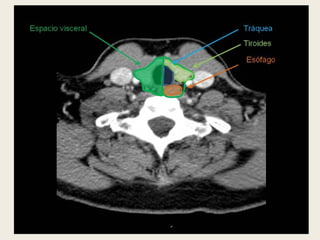

ESPACIO VISCERAL

 Se delimita por la

capa media de la

fascia cervical

profunda.

 Contiene el tiroides, el

paratiroides, la

tráquea, el esófago, los

ganglios

paraesofágicos y los

nervios laríngeos.